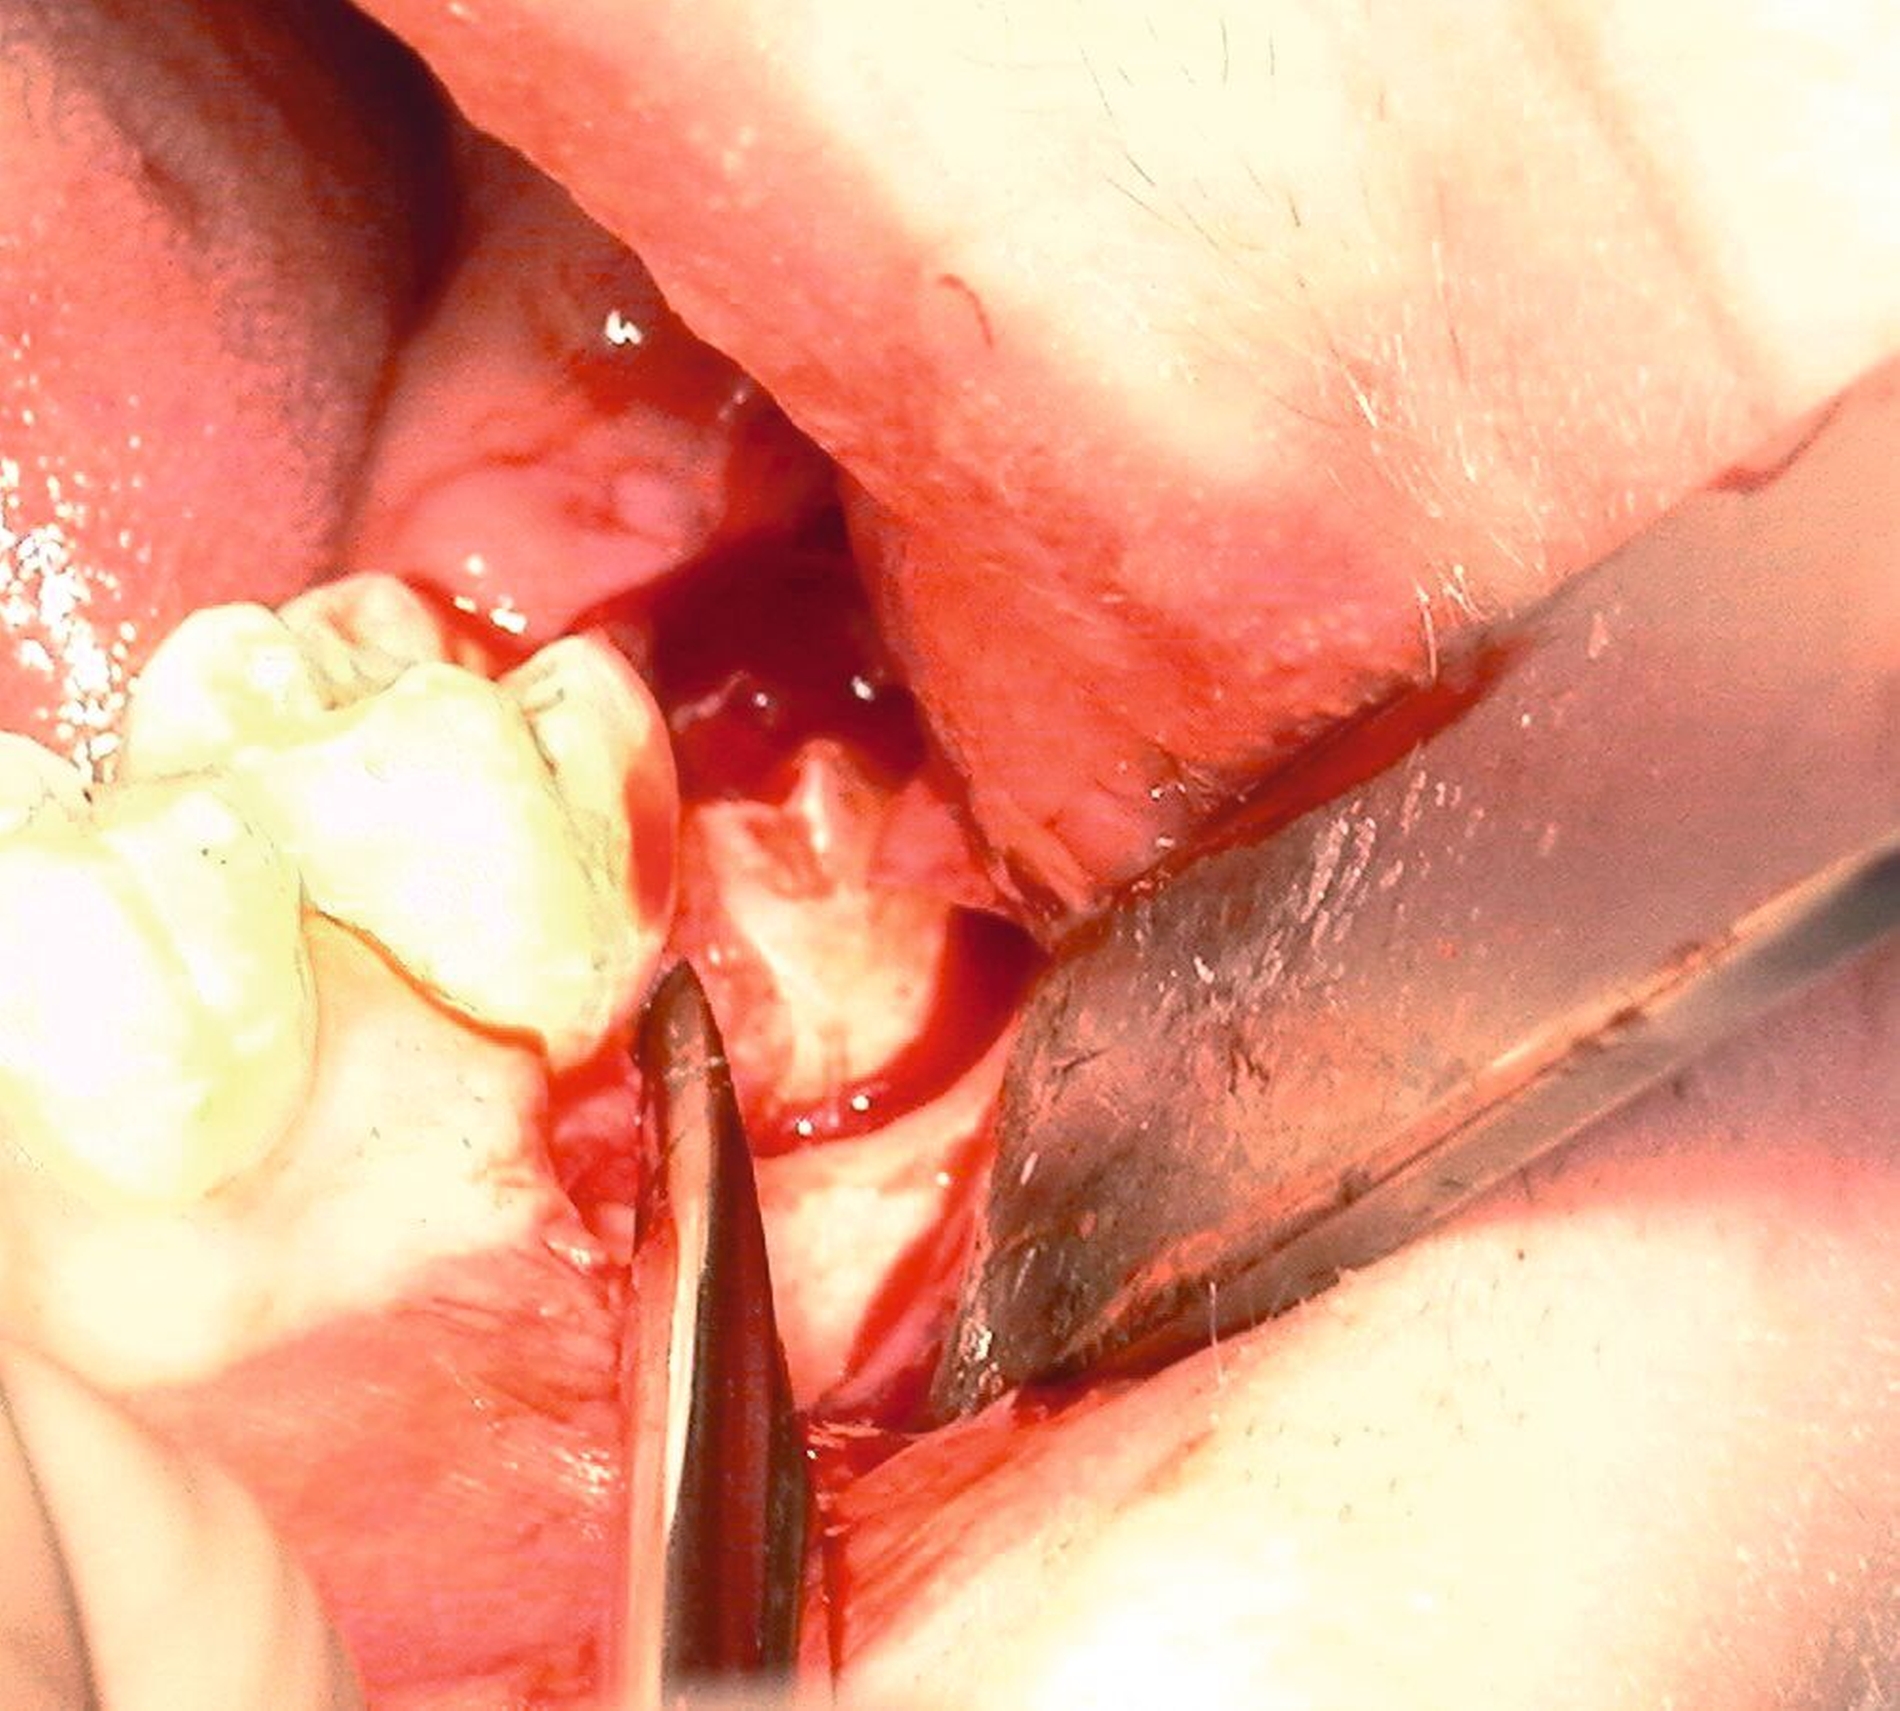

Nach Freilegung des Knochens kann ein Wundhaken nach Langenbeck eingesetzt werden sowie ein Bohr-Raspatorium zum Schutz des N. lingualis subperiostal lingual [Gutwald et al., 2019]. Unter Verwendung eines rotierenden Instruments (Kugel- und Lindemann-Fräse) oder Piezochirurgie wird der Knochen im Bereich der Zahnkrone abgetragen und diese freigelegt (Abbildung 8). Danach kann der Weisheitszahn vorsichtig mithilfe eines Bein‘schen Hebels anluxiert oder, falls dies noch nicht gelingt, mittels einer Lindemann-Fräse geteilt werden. Dabei wird am größten Kronendurchmesser die Krone mit der Fräse abgetrennt und die Wurzel anschließend separat entfernt (Abbildungen 9 und 10) [Gutwald et al., 2019; Schwenzer, 2019].